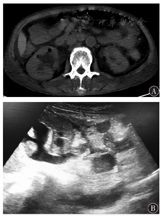

患者女,67岁,因"发热伴腰痛、少尿3 d"于2018年6月28日入院。患者入院前3 d发热,体温38.5℃,伴腰痛、少尿,于当地医院就诊。心电监测:P 130次/min,BP 108/74 mmHg。血常规:WBC 14.47×109/L。尿白细胞6897个/HP,细菌6589个/μl。Scr 180 μmol/L,BUN 13.7 mmol/L,Glu 21.8 mmol/L。腹CT:双肾增大,肾盂扩张,右肾气体密度影。初步诊断:泌尿系感染,急性肾损伤,2型糖尿病。予头孢哌酮舒巴坦、亚胺培南西司他丁抗感染及补液、降糖治疗。患者出现休克,少尿。6月27日血WBC 30.93×109/L;Scr 185 μmol/L,BUN 17 mmol/L。尿量300 ml/24 h。遂转诊至本院重症监护病房,入院诊断:EPN合并MODS。既往有2型糖尿病,糖尿病视网膜病变病史10年,未予监测及控制血糖。有反复泌尿系感染病史,自行口服抗生素治疗。去甲肾上腺素泵入。查体:T 39℃,P 110次/min,BP 100/60 mmHg,R 20次/min。嗜睡,贫血貌。心肺腹查体未见异常。血常规:WBC 34.4×109/L,Hb 86 g/L,Plt 54×109/L。血乳酸(Lac)4.9 mmol/L,Scr 166 μmol/L,BUN 18.68 mmol/L,Glu 15.5 mmol/L,Na+ 129.8 mmol/L。腹部CT示:双肾增大,双肾及输尿管扩张、积水,右侧肾盂及肾皮质见气体密度影。见图1A。泌尿系超声检查示:左肾集合系统分离1.0 cm,右肾集合系统分离1.7 cm,双肾盂内见絮状中等回声,范围分别为2.8 cm×1.4 cm及2.9 cm×1.5 cm,输尿管上段扩张1.1 cm,输尿管内见絮状中等回声,范围2.5 cm×1.0 cm,中等回声内均未见血流信号。见图1B。临床诊断:(1)气肿性肾盂肾炎;(2)感染性休克;(3)急性肾损伤;(4)代谢性酸中毒,电解质紊乱,低钠血症;(5)2型糖尿病;(6)贫血(中度)。治疗及随访:予美罗培南、利奈唑胺抗感染,输血、补液、升压,降糖等治疗。6月29日超声引导下右肾盂穿刺置管引流术,引出大量白色絮状物及少量白色团块。引流液离心后得灰白色沉渣两枚,病理检查结果提示为光滑念珠菌孢子及菌丝。2次尿液、引流液及血培养均为光滑念珠菌,药物敏感试验结果提示伏立康唑、两性霉素B敏感。2次G试验大于70 ng/L。立即予静脉点滴伏立康唑,两性霉素B局部灌洗。7月6日患者签字出院,院外序贯予伏立康唑口服。随访1个月,患者病愈。

注:A:CT;B:B超